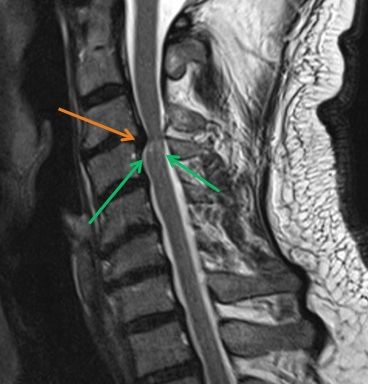

Kernspintomographie (MRT): Bandscheibenvorfall in der Halswirbelsäule

Cervikale Myelopathie (grüner Pfeil) durch Bandscheibenvorfall ( roter Pfeil)